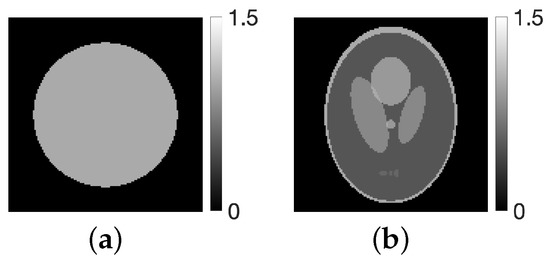

4.1. Experimental Method

4.2. Experimental Results